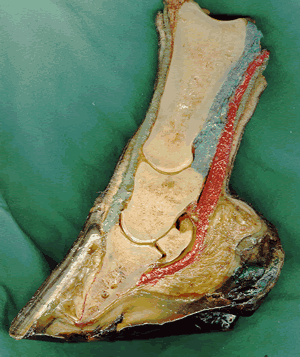

Pferd: Arthrosen, verschiedener Gelenke hierzu zählen auch Spat, Hufrolle,.

Erkrankungen der Wirbelsäule , hierzu zählen Spondylose, cauda equina, kissing spines.